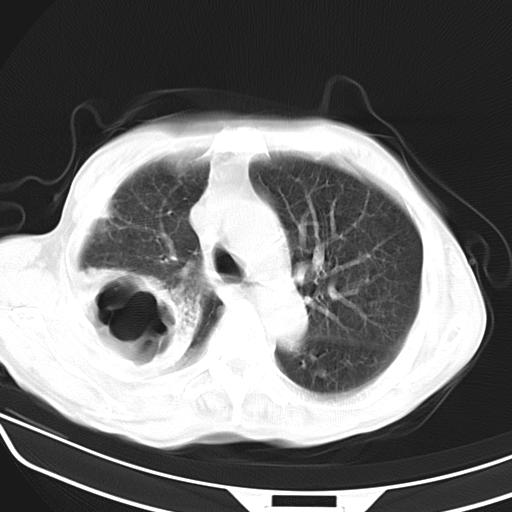

抗炎治疗10天后复查

抗炎治疗10天后复查:右上肺模糊阴影明显减少。

诊断意见:考虑右上肺巨大含气囊肿并感染,建议继续治疗后复查。